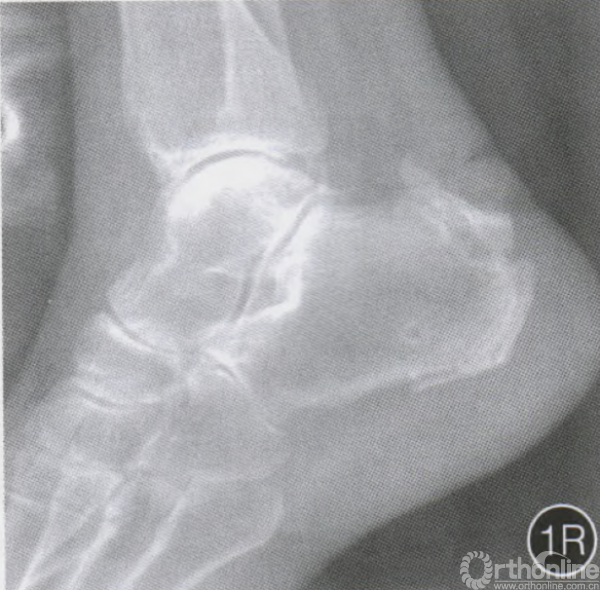

术后6周复查X线片示骨折已愈合(R)

急诊予右踝跖屈位石膏固定。伤后第6天,局部软组织肿胀消退,行手术治疗。手术采用硬膜外麻醉,患者取俯卧位,屈膝15。,术中驱血并使用止血带。通过触诊确定跟腱止点跟骨撕脱骨折区,于跟腱止点远端两侧行长约5—10mm的纵形切口,切开周围组织并作适当分离,用1枚带孔克氏针穿上可吸收缝线于跟腱止点近端横穿跟腱,由此线牵引抗高张力缝线折成的双线穿过止点近端跟腱(图1c,D),并将线环和线尾由跟腱止点远端两侧切口引出(图lE,F);经皮于跟骨近中央部钻孔,注意保护两侧皮肤,由此孑L引人多股双线,并通过跟腱止点远端切口预留缝线将各股双线的线环及线尾由一侧切口引出(图1G~0),此时应用牵拉及Nice Knot缝线技术将跟骨骨折块及撕脱的跟腱止点捆扎固定(图1P,Q),缝合切口,加压包扎。术后右下肢及右踝关节支具固定,4周内免负重。随后嘱患者在右足跖屈位部分负重,随后恢复至正常负重,术后6周复查示患者骨折愈合良好(图1R),患者未诉骨折区疼痛或不适。